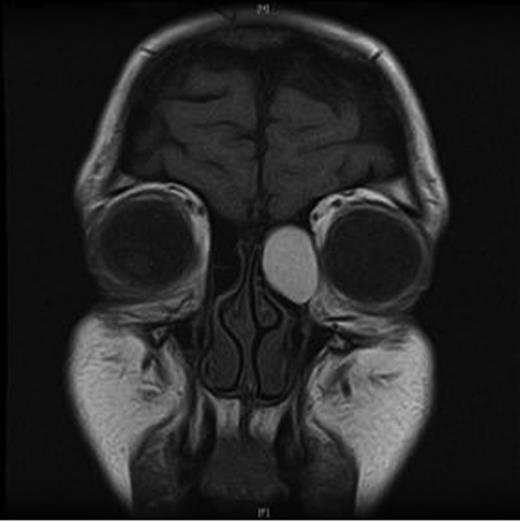

Clinical examination revealed a small cystic swelling in her left medial canthus (Fig. 1). There was no discharge on pressure, mild tenderness was elicited and the swelling was not compressible. The rest of the eye examination was normal with a visual acuity of 6/6 in both eyes.

An MRI scan of the orbits showed a well-defined, thin-walled 22 × 16 mm cyst medial to the left orbit containing fatty/proteinaceous material, which was lying within and mildly expanding the left ethmoid air cells (Figs 1–3).